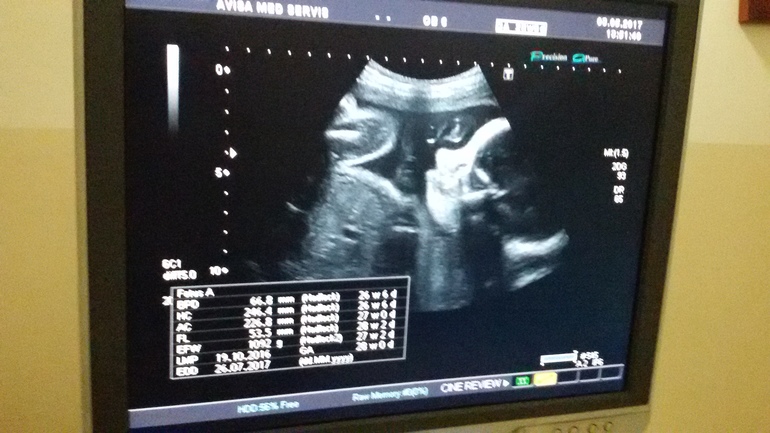

и для собственного успокоения пошла на доплер. кровоток хороший. дите лежит правильно, развиваеться по срокам и в наглую лежит и чешет яйки правой ручкой)) мужик растет))))

узист тоже мужчина-долго смеялся))) что бы хлопали в ладоши- видел, махали ручкой- видел, пинался, икал, зевал- видел... но что бы яйки чесал))))))) вообщем весело было. еще дитешь долго возмущался что его снимают и ножкой отпиновал узиста)))

слава богу нет гипоксии, воды чистые и обвития нет. шовчик глянули- 7 мм. сказали хороший очень, однородный. это меня очень порадовало.

ну и фото с доплера, как получилось сфоткат ь так и сфоткала- для истрии подойдет, правда страшненький он на нем получился, ну на каком ракурсе поймала, уж извините) и фото пузяньки